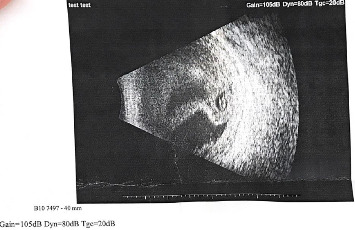

Abstract Image